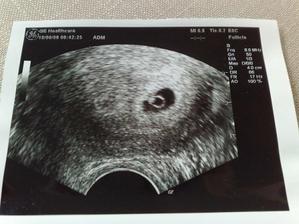

Od poslední operace jsem užívala Utrogestan po něm mi nebylo moc dobře, tak se nasadila Provera.Po ní mám stejně MS nepravidelnou.Koncem května jsme se rozhodli navštívit Car.Chtěli jsme do Zlína, pač to máme blíž, ale moje pojišťovna s nimi nemá slouvu, takže nic.Takže jsme hledali a našli si v Olomouci Fertimed.Objednali jsme se na konzultaci 2.7.2008.Konzultace proběhla bez problému, jen vyšetření, které proběhlo před přítelem bylo pro něj trochu překvapením.Příteli udělali SPG kde zjistily že je v pořadku.Posléze nám byli zjištěny Ureoplazmata, tak jsme s přítelem zobali ATB. Nebylo nám ani jednomu znich dobře. A měli jsme zakázáno snažilkování. 20.8.2008 jsem měla jít na svou první IUI, ale bylo mi zjištěno, že nemám ovulaci.Tak s toho sešlo.9.9.2008 jsem měla vyšetření průchodnosti.12.9.2008 jsem šla na KO a na výsledky.Vše je ok, vše mám průchodný i po všech operacích a ureoplazmatech.A snažilkování opět zakázáno kvůli zahojení.Poprvé mi byly dány stimulace Clostilbegyt.Tak teď už jen čekám na mrchu.Mrcha dorazila 3.10. takže opět smůla,7.10. začínám zobat Clostilbegyt.Po sexíku po něm trochu špinim, ale je to možná ještě brzy kvůli tomu vyšetření průchodnosti. 13.10. jedu do Car na KO hm tak jsem zvědavá jak to na mě zapůsobilo.Uvidíme co budu mít v bříšku 🙂) KO dopadla dobře mám 4 vajíčka o velikosti 1.4cm a sliznici 5.5cm. 17.10.08 v 13hod máme první inseminaci.Po píchnutí pregnylu mi není dobře a ještě k tomu ten divný klobouček co zavádějí.19.10. kontrola a druhá inseminace.29.10. Kontrola v CAr a nalezena další cysta.Další cyklus tedy proběhne bez Clostíku.19.11. kontrola máme ovulaci a 2 folikuly.24.11. třetí inseminace opět je mi špatně po pregnylu a ten klobouček hrůza 26.11. čtvrtá inseminace opět je mi špatně po pregnylu, odebrána krev na tumorové markry,štítnou žlázu a cytologie.5.12. kontrola není nic vidět, krev v pořádku aspoň se nemusím bát že mám v sobě rakovinové buňky,štítná žláza též v pořádku.Cytologie bude po Vánocích.Přes Vánoce nepracují tudíž se budeme snažilkovat doma.Přes Vánoce jsem si zkoušela porvé udělat ovulační testy.Testy mi vycházely // jeden mi vyšel i s /// což bylo tedy opravdu divné.5.1.09 jsem si udělala poslední ovu test s// nu jenže 6.1.09 jsem dostala pěkně silnou MS.12.1.09 jsem byla u své obvoní dr, která mi vzala krev a moč.13.1.09 jsem byla u své gynekoložky a ta mi řekla že jsem měla opět cystu která byla už prasklá.Moje obvodní lékařka mi řekla ,moč je v pořádku,ale v krvi mi chybí červené barvivo v červených krvinkách.Tak jsem si koupila železo s kyselinou listovou.21.1.kontrola v CAR řekli mi že mám 2folikuly, odmítla jsem IVF, a objednala se do FN Olomouc (10.března 11:45) k dr. Dostálovy, výsledky z cytologie dopadly dobře. 10.3. první poradna u doc.Dostála, vše probíhalo v pořádku, zatím jsme jen dotsali papíry na IUI. 23.3. 13dc sliznice 10mm, ovarium vlevo 14+PCO, ovarium vpravo 17mm, 25.3.-27.3. plánovaný styk. 21.4.09 13dc sliznice 10,3mm, vpravo 19x26mm folikl, dnes IUI, následující den plánovaný styk,zavádění Utrogestanu po 8dní. 13.5. poradna s doc. Dostálem, výsledky horm. profilu ok, spg ok, domluva na IVF ( srpen 09 ), dostala jsem veškeré léky a poučení. 18.5. 13dc sliznice 11mm, ovarium vlevo 17mm, vpravo nic, 19.-20.5.09 plánovaný styk.21.5. UTZ sliznice 7,4mm, ovaria 0, 1.6.09 HCG 103,9. 18.6.09 UTZ 6tt embryo s pravidelnou akcí srdeční. 25.6.09 UTZ 7tt vše ok. 9.7.09 UTZ 9tt těhu průkazka. 3.8.09 Prediko UTZ 13tt vše ok jen nemáme změřenou nosní kůstku. 6.8.09 13tt kontrola, 26.8.09 16tt kontrola 1,5kg, 10.9.09 18+1 kontrola 0,5kg, 24.9.09 20+1 kontrola první pohyby 2,5kg, 25.9.09 Prediko UTZ 20+2, 15.10.09 23+1 1,5kg, 2.11.09 test na cukrovku už nikdy v životě!, dietu nedržím ale musím chodit na ko, 5.11.09 26+1 2kg,